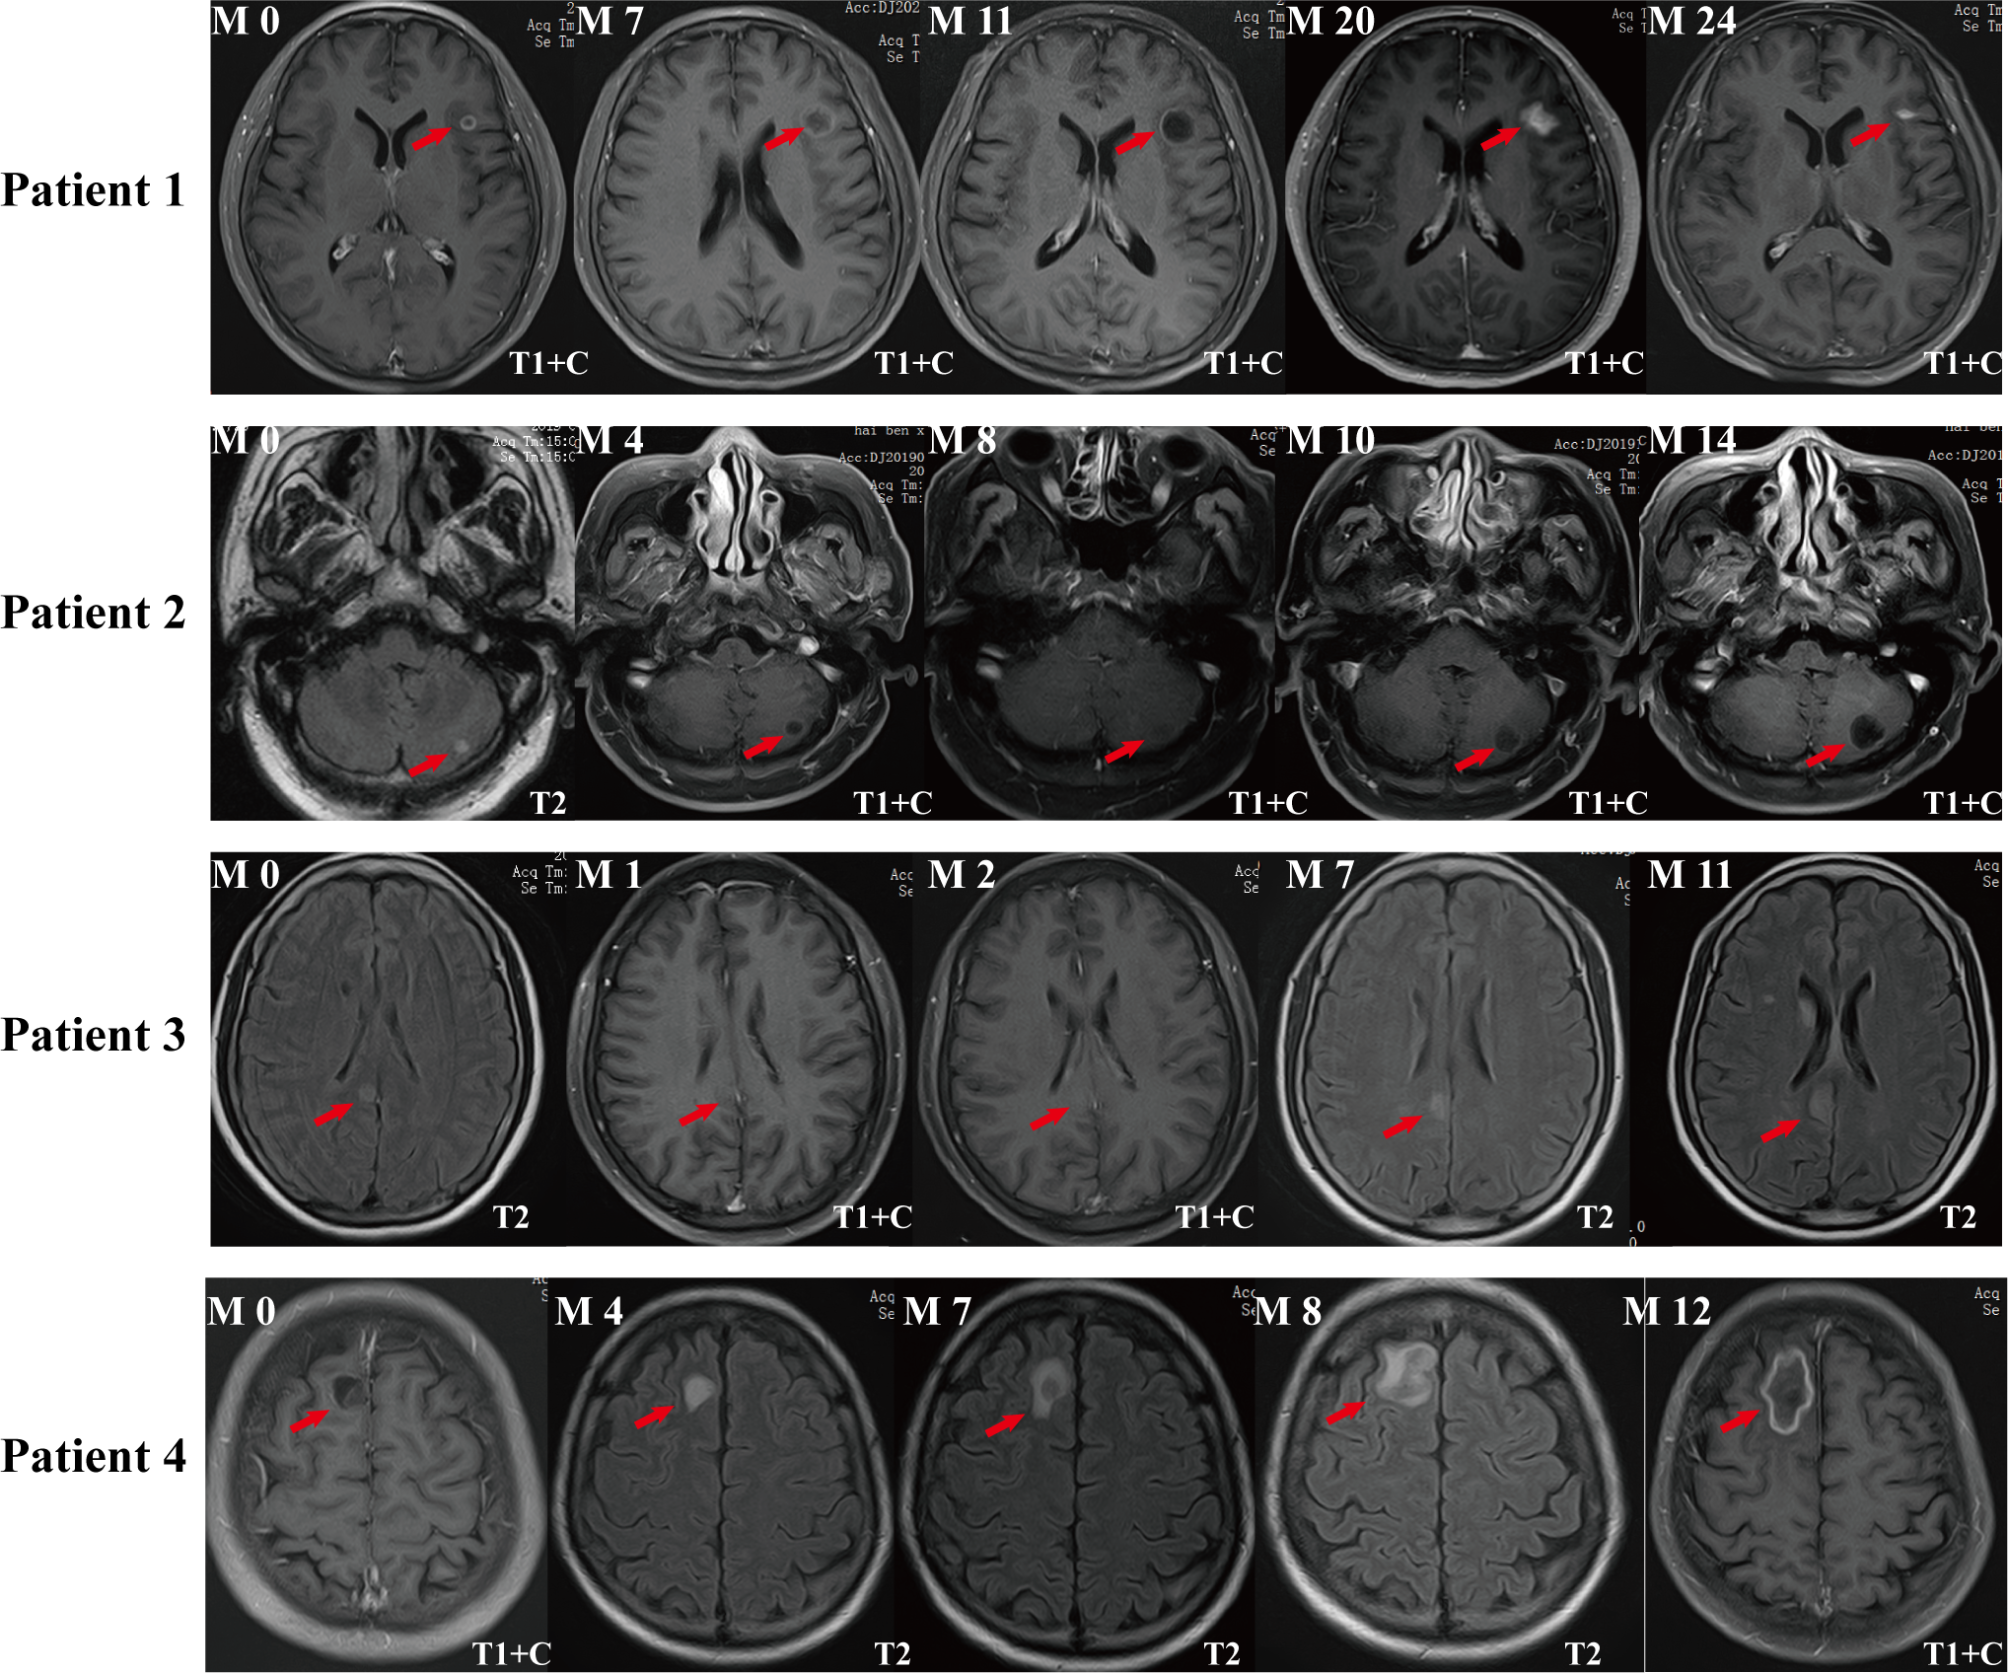

Fig. 1

From: Longitudinal MRI evaluation of the efficacy of non-enhanced lung cancer brain metastases

Follow-up MR imaging characteristics of non-enhanced BM during treatment. Patient 1, Female, 57-year-old, invasive adenocarcinoma of left inferior lobe of lung. The patient underwent chemotherapy, targeted therapy, immunotherapy, radiotherapy and other comprehensive treatment. The figure shows axial enhanced T1-weighted MR image of left frontal lobe brain metastases. Patient 2, Male, 69-year-old, adenocarcinoma of left inferior lobe of lung. He was treated with chemotherapy, targeted therapy, radiotherapy and other comprehensive treatment. The figure shows the axial T2-weighted and enhanced T1-weighted MR image of the left cerebellar metastatic tumor. Patient 3, Female, 59-year-old, adenocarcinoma of right lung. She was treated with chemotherapy, immunotherapy, radiotherapy and other comprehensive treatment. The figure shows axial T2-weighted and enhanced T1-weighted MR images of the right parietal lobe metastasis. Patient 4, Male, 47-year-old, adenocarcinoma of upper lobe of left lung. He was treated with chemotherapy, radiotherapy and targeted therapy and other comprehensive treatment. The figure shows the axial T2-weighted and T1-weighted MRI images of right frontal lobe metastases. Note The follow-up time was marked in the upper right corner (Month), the MR scan sequence was marked in the lower left corner, and the red arrow showed the metastatic focus.